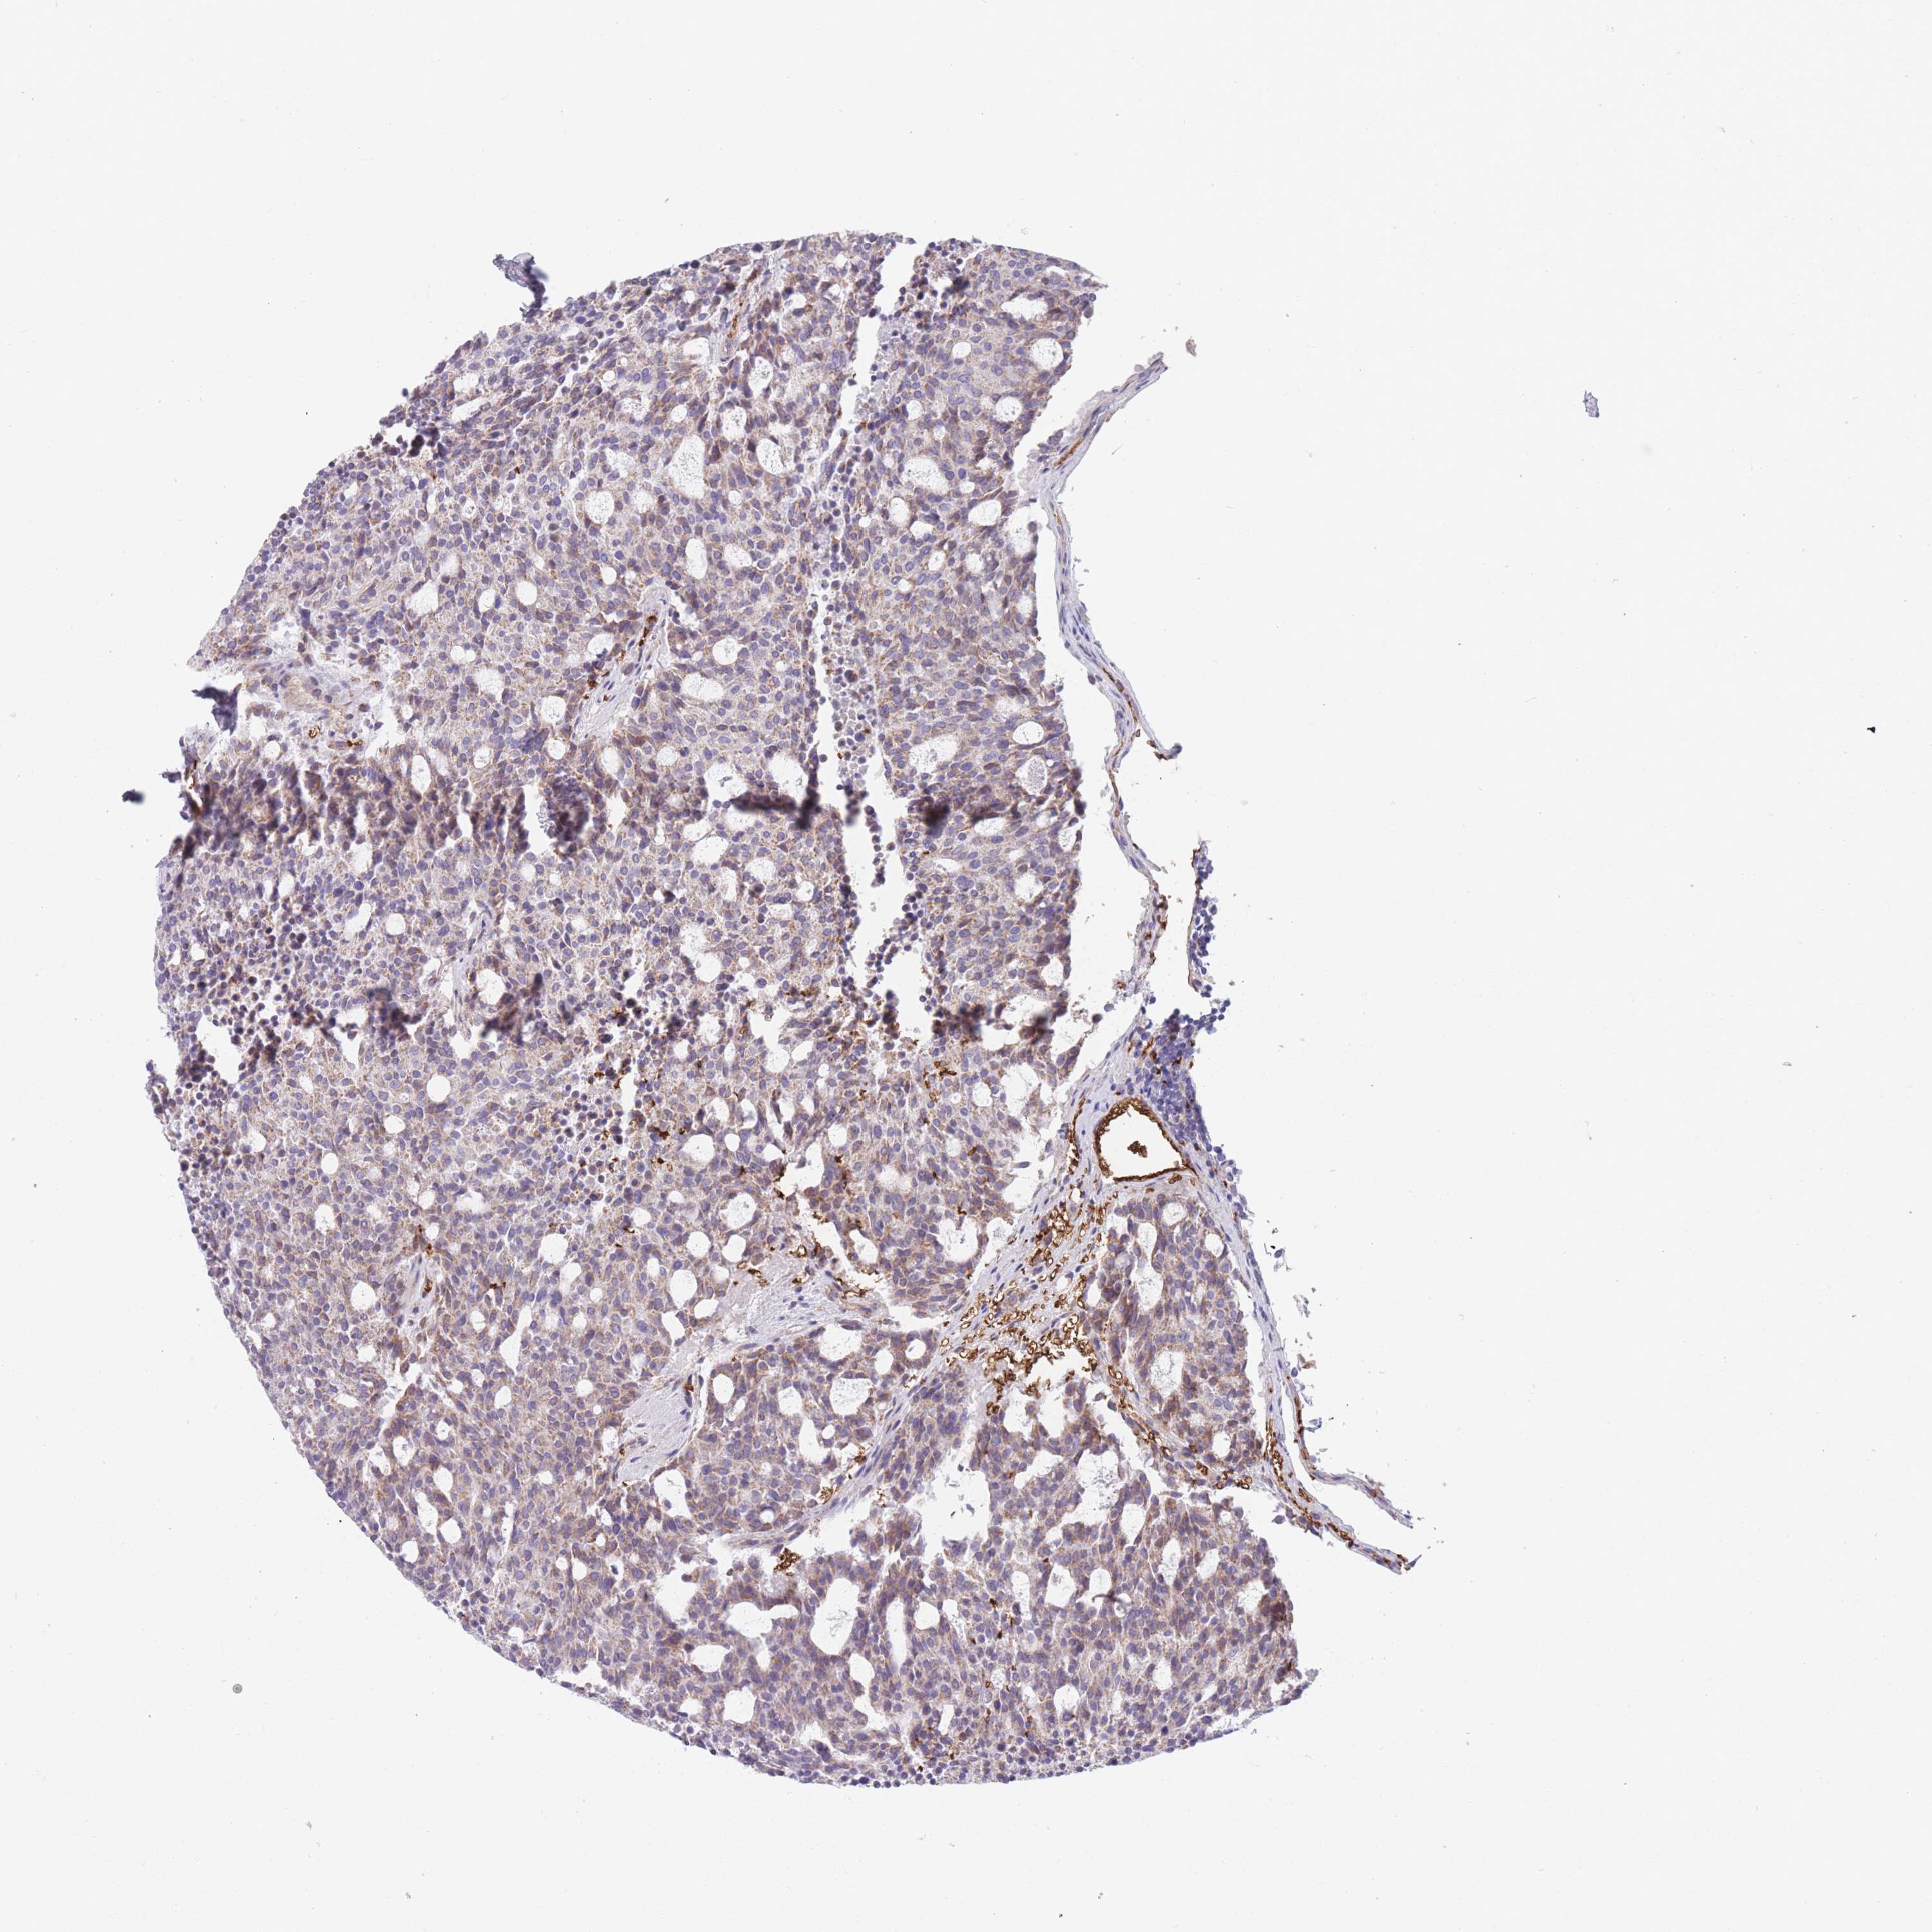

Neuroendocrine tumors

Human pathology

Carcinoid